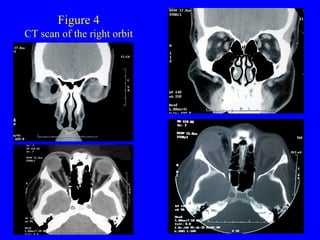

New England Eye Center Grand Rounds  Dilated fundus examination on the right revealed a normal disk, macula, and vessels.  In the superonasal quadrant, there was a small area of intraretinal hemorrhage over an area where the globe was indented from the orbital foreign body. CT scans (figure 4) revealed an intraorbital foreign body isodense with air, extending from the medial upper lid toward the orbital apex. The globe was indented and displaced inferotemporally. The orbital bones were completely intact, without any fractures.

Figure 4 CT scan of the right orbit